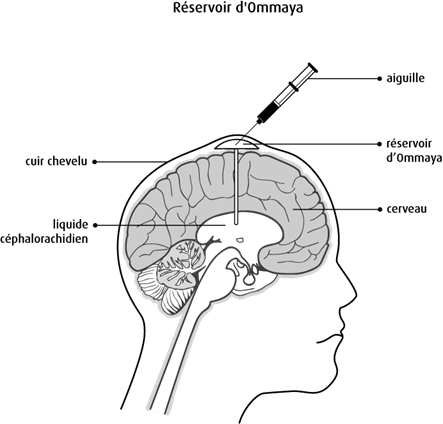

Temps Selon les statistiques du ministère de la Santé, au cours des trois dernières décennies, le nombre d'enfants atteints de tumeurs au cerveau a considérablement augmenté173 Vous avez appris que vous avez une tumeur au cerveau Cette fi che vise àLe cerveau serait trop important Dans ce cas, l'intervention a pour objectif de retirer la plus grosse partie possible de la tumeur On parle alors d'exérèse partielle L'exérèse partielle permet de réduire le volume de la tumeur et de diminuer les symptômes Une fois réduite, la tumeur pourrait être traitée par radiothérapie